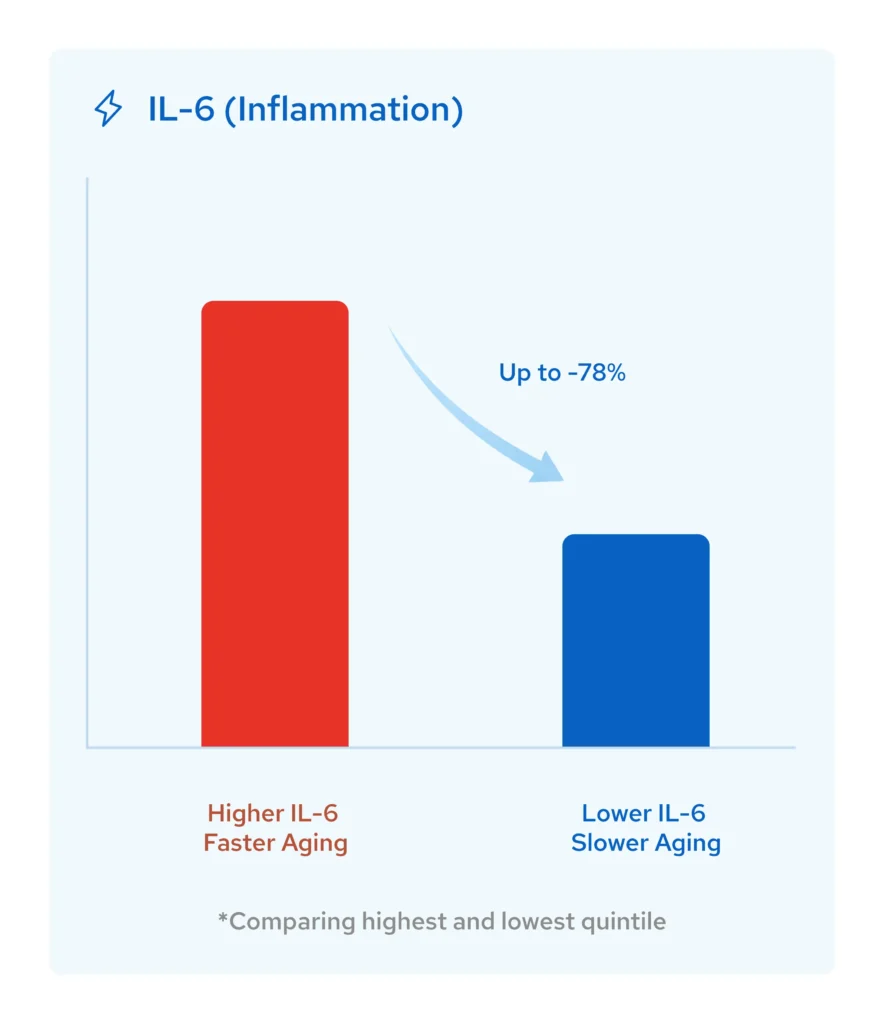

Reduces Chronic Inflammation: The Root of Accelerated Aging

Inflammation is the silent accelerator of aging.

It damages cells, impairs recovery, and drives age-related diseases like cardiovascular decline, cognitive deterioration, and metabolic dysfunction.

In a scientific study, Nurosym’s vagus nerve stimulation activated the cholinergic anti-inflammatory pathway, reducing systemic inflammation by up to a 78% reduction in IL-6 harmful cytokines (Dasari 2023).

And what does it mean?

Lower inflammation means slower aging at the cellular level.